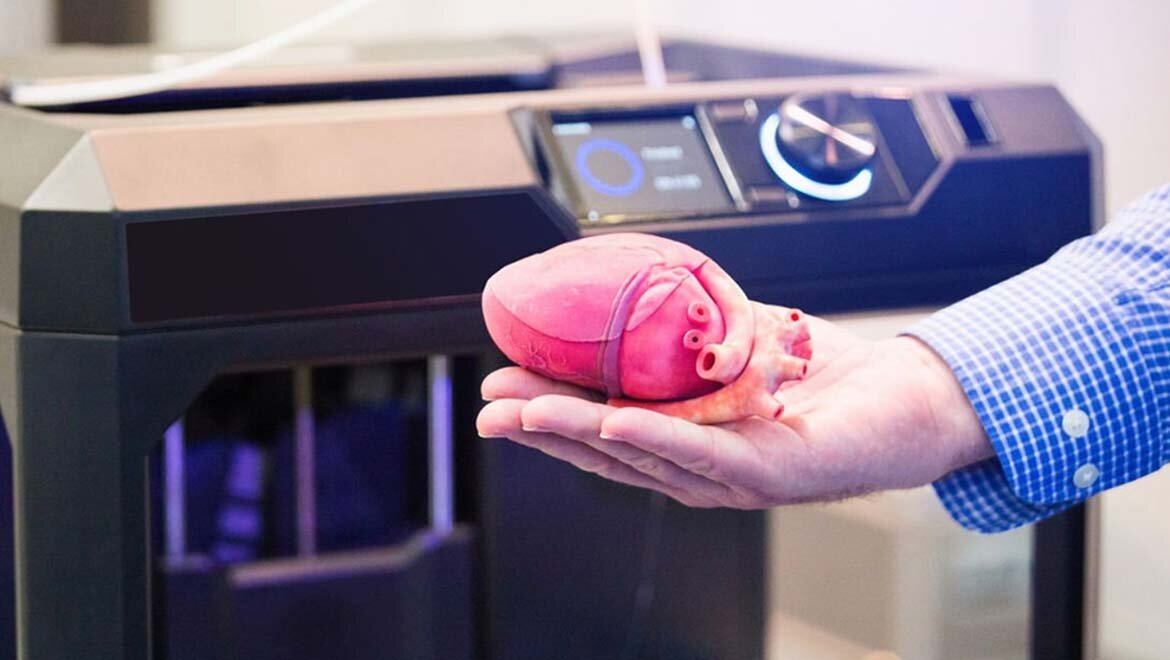

3D printed organs. This is a modern example of a technology that would easily be available to an ancient society that could "enslave" mammals and modify their DNA. These are not alchemies. It's not a ceremony. Programming Genes is a mathematical and a science, not the mystery that it became.

Hearts, skin, any portion of the body could be printed, just like a machine. Specs could be shared and this engine could be waiting in a car that is built while your at a dinner.

This is advanced for us, today. It is a primitive solution when genes themselves could be programmed to make this repair based on the holographic/magnetic image around all living things and even seeds.